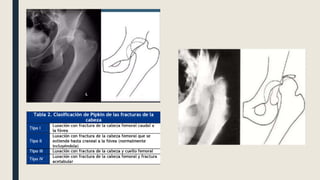

EPIDEMIOLOGIA ■ URGENCIA ORTOPEDICA!! ■Lesión grave e infrecuente (2-5%) ■ Luxación posterior asociada a fractura de cabeza femoral 6-16% ■ Trauma de alta energía (trafico) ■ Posterior (traumatismo anteroposterior con cadera y rodilla en flexión / salpicadero) ■ Anterior (hiperabducción + hiperextensión) ■ Centrales (traumatismo directo sobre el trocánter mayor) ■ Cadera en menor aducción o menor rotación interna = fractura-luxación tipo Pipkin o de muro posterior de acetabulo